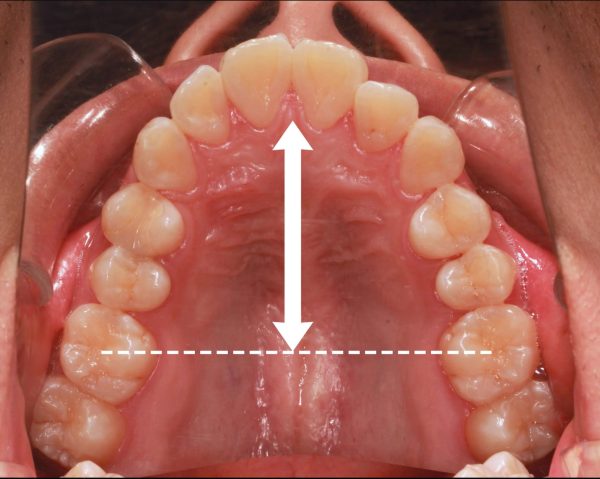

口ゴボ治療前

歯の1本、1本が標準のサイズよりも大き過ぎるため、前に押し出されて 歯ならびが通常より 前後に長いです。

この影響で ”出っ歯” になっていています。

このため、口もとが出ていて、あごが 無いように見えます。

抜歯を行ったことで、前歯が下がり、上顎の前後的な距離が適正になりました。

口ゴホ治療前後

同じように 下あごも前後的な距離が短くなり、適正な長さになりました。

上下の顎が適正な長さになった、この効果で上下の前歯が下がりました。